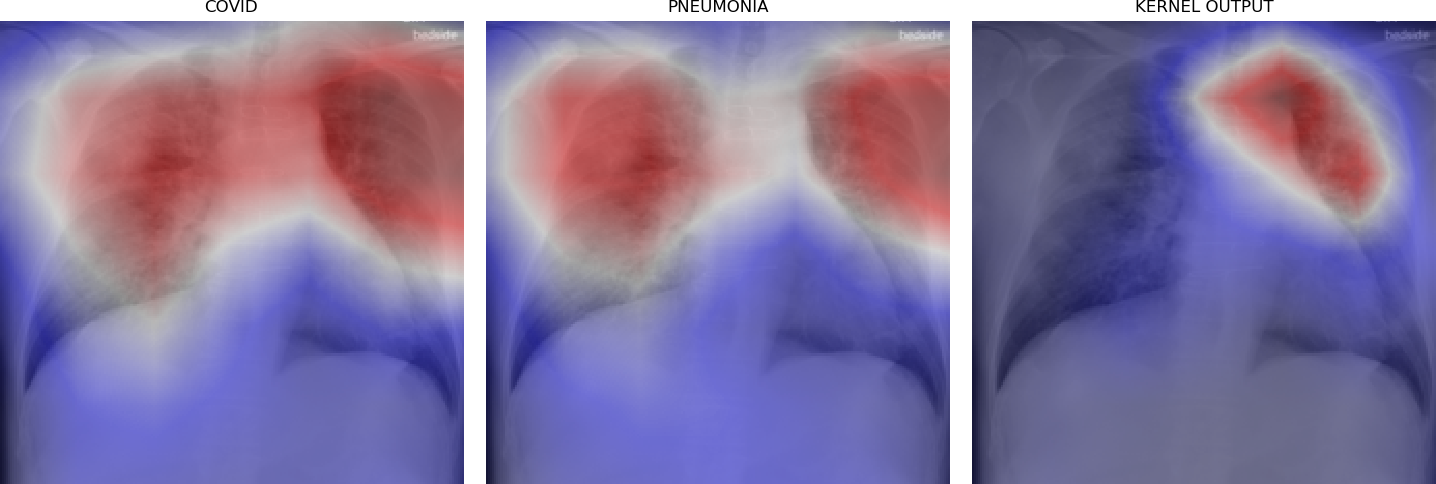

Figure 5 shows triples of X-ray images with superimposed class activation maps for predictions obtained from expert binary models (images one and two) with the third image showing the heat maps computed using our kernel. The intended use of our method is to examine positive classifications from two possibly overlapping classes (i.e. COVID-19, Pneumonia) and extract discriminative features pertaining to the class of interest, i.e. COVID-19. Triples (a)-(f) show positive classifications of COVID-19 and Pneumonia by their respective binary expert models along with class activation maps that localize the image region responsible for that classification. The third image in each triple shows a better localized image region for COVID-19 as computed using our method. Our method is intended to improve explainability of predictions under circumstances where both models return positive classifications resulting in significant overlap in activation maps.

Figure 6 demonstrates the role of the kernel parameter . It controls amplification of the directed differences among the activation maps. Higher values of concentrate the resulting heat map to a smaller region.